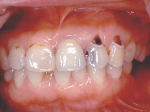

インセラム(オールセラミック)症例②

治療前治療前術前 治療後治療後術後 歯の尖端の透明感までよく再現できている。